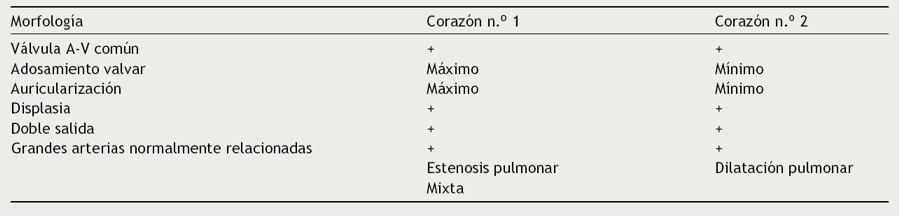

Figura 1 Vista interna de las cámaras derechas de un corazón con concordancia auriculoventricular y anomalía de Ebstein de la válvula tricúspide. El anillo fibroso está situado en la unión auriculoventricular (asteriscos). Obsérvese el adosamiento de las valvas septal y posterior a las paredes ventriculares, la valva anterior es redundante. AD: aurícula derecha; I: infundíbulo; VA: válvula anterior; VD: ventrículo derecho; VP: válvula posterior; VS: válvula septal.

Al comparar los corazones descritos en este trabajo con los que presentan anomalía de Ebstein de la válvula tricúspide con conexiones auriculoventriculares concordante y discordante se observan diferencias entre ellos. En la anomalía de Ebstein con conexión auriculoventricular concordante el adosamiento se presenta en forma de un espectro de grados de severidad con nodulaciones fibromixoides en las valvas liberadas, cuerdas tendinosas cortas y engrosadas y músculos papilares de estructura fibrosa o ausentes (Fig. 1). En la anomalía de Ebstein con discordancia auriculoventricular el adosamiento de la valva septal es de menor extensión y afecta solamente a esta valva (Fig. 9) y cuando esta malformación valvular se asocia a corazones con conexiones auriculoventriculares univentriculares, el adosamiento valvar puede ser extenso o solo en las porciones proximales (Figs. 6 y 8).